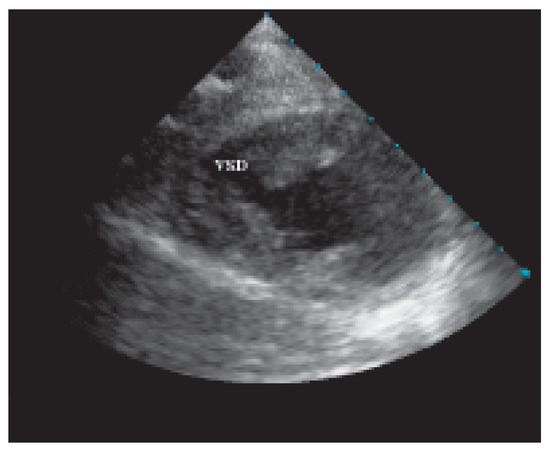

Traumatic Tamponade and Ventricular Septal Defect

A 30-year-old man sustained a knife wound in the 9th left intercostal space when he was involved in a fight as a bodyguard in a night club [...] Full article

Show Figures

Figure 1